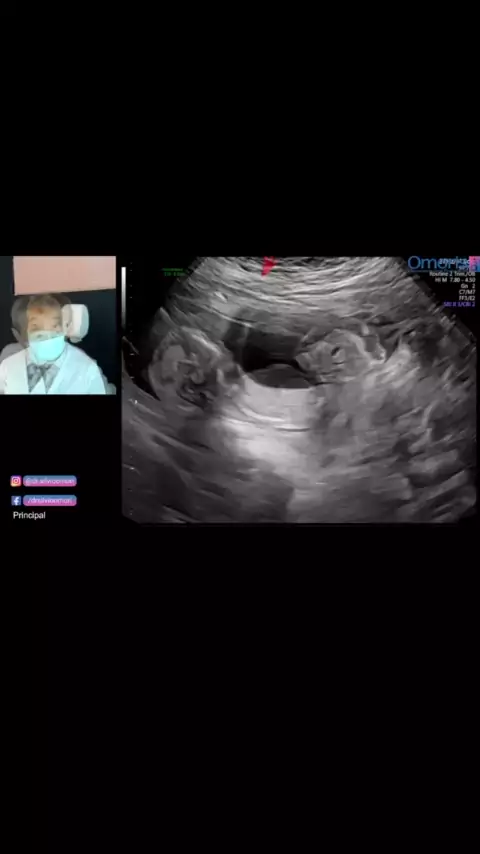

dr.silvioomori

gravidez com DIU!! #diu #👶🏻bebe #Mae #ultrassom #gravidez